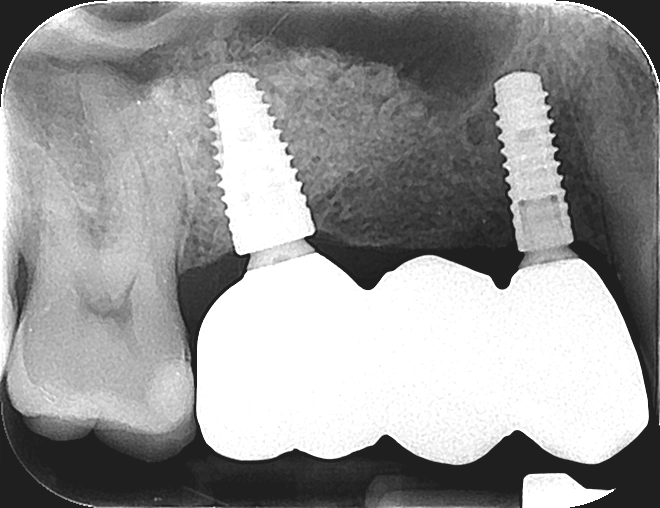

Before

After